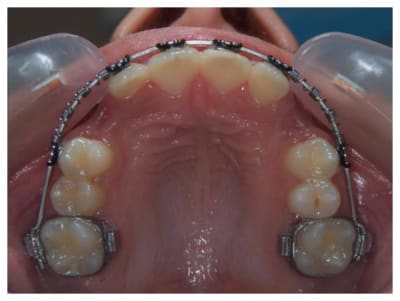

Je pense qu'il est tout à fait possible de trouver la place pour les prémolaires et cela vaut le coup de tenter avant d'extraire quoique ce soit.

Multi attaches uyazzt - Eugenol

Maintenant, on aimerait voir les faces occlusales des dents, et aussi un peu la forme du visage.. S'il y avait une télé, ce serait bien aussi.

Dans cette phase d'interception, le Qhelix et la FEO me semblent pas mal.

Par contre, regardez la différence de taille des couronnes des secondes molaires temporaires par rapport aux deuxième prémolaires. Cela donne de la marge supplémentaire à l'orthodontiste pour éviter des extractions.